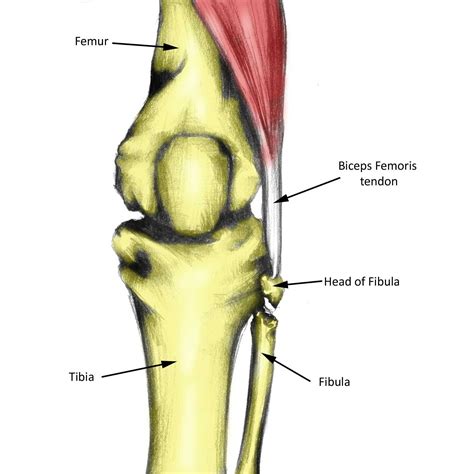

Understanding Biceps Femoris Tendinosis

Biceps Femoris Tendinosis is a degenerative condition that affects the tendon of the biceps femoris muscle, one of the three muscles that make up the hamstring. This condition is characterized by the degeneration of the tendon tissue, leading to pain and weakness in the back of the thigh. It is often caused by repetitive stress and overuse, making it common among athletes involved in sports that require sudden stops, starts, and changes in direction, such as soccer, basketball, and track and field.

Diagnosing Biceps Femoris Tendinosis

Diagnosing Biceps Femoris Tendinosis involves a combination of physical examination and imaging tests. A healthcare professional will typically:

• Imaging Tests: Order imaging tests such as ultrasound or MRI to visualize the tendon and confirm the diagnosis. These tests can help identify degeneration, thickening, or other abnormalities in the tendon.